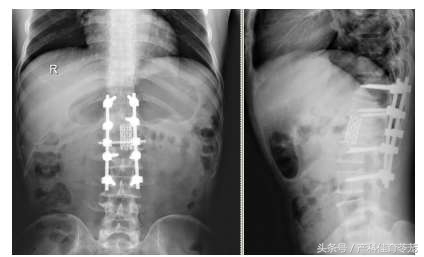

翻修手术去除了椎管内的骨块,解除神经压迫;调整螺钉位置;植入了钛网,重建脊柱稳定性,为神经功能恢复夯实了基础。